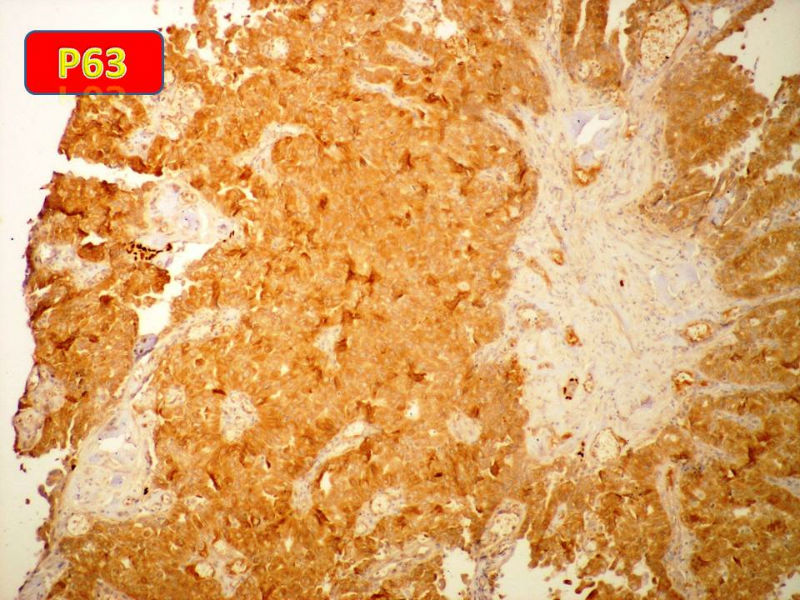

只能说是乳头状瘤

是不是导管内

乳头状瘤 and 导管内乳头状瘤 are the same; Benign lesion.

After you work up and you still cannot be sure it is benign , atypical or maignant lesion, you can call 乳头状lesion.

If this is excisonal case, you should figure out the nature of the papillary lesion.

我的意思就是提醒大家 在不是很确定的情况下 尽量少给自己套枷锁